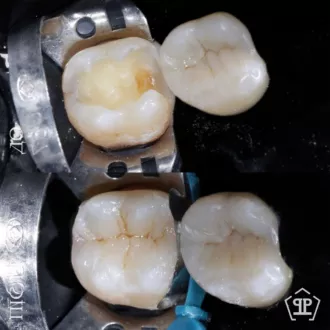

Пациент обратился с жалобами на повышенную чувствительность к воздуху и сладкую пищу в области угловых зубов. После обследования и диагностического разбора КТ был диагностирован глубокий контактный кариес 14 и 15 зуба. Произведено изолирование зубов кофердамом, с последующим раскрытием кариозных полостей и последующим восстановлением утраченных тканей методом художественной реставрации.